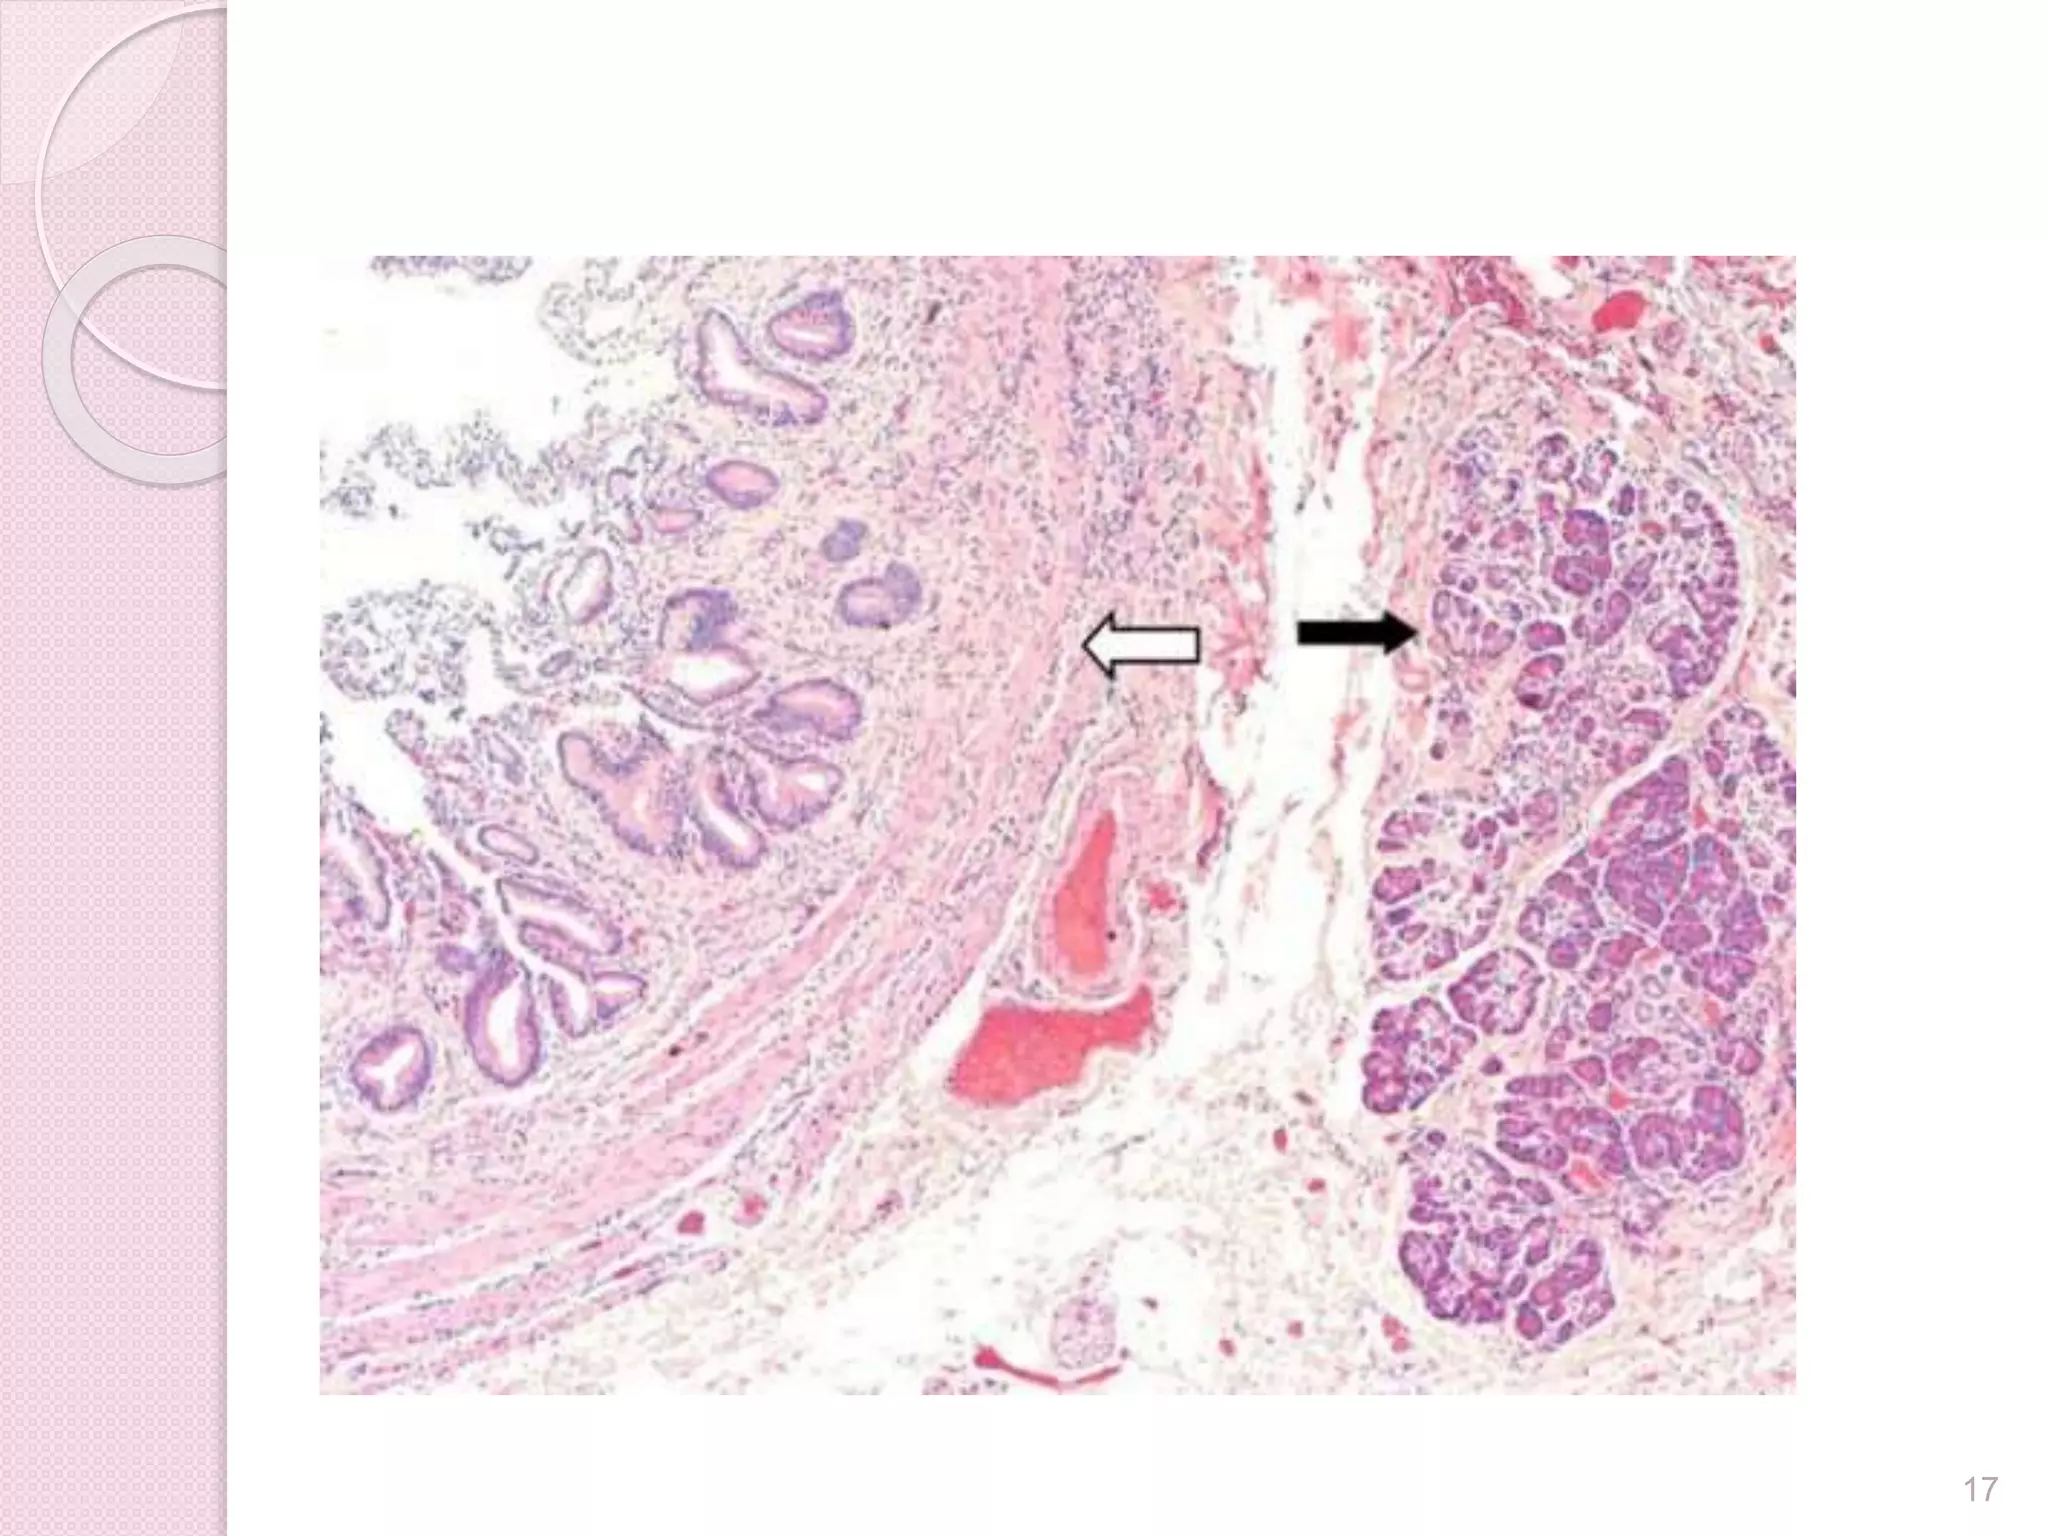

Pancreatic heterotopia

● Also called ectopic pancreas

● Present in 0.5% to 14% of autopsies

● Due to displacement of pancreatic

tissue during embryonic development

16

Pancreatic heterotopia  Pancreatictissue outside boundaries of pancreas without anatomic or vascular connections to pancreas ● Also called ectopic pancreas ● Present in 0.5% to 14% of autopsies ● Due to displacement of pancreatic tissue during embryonic development 16